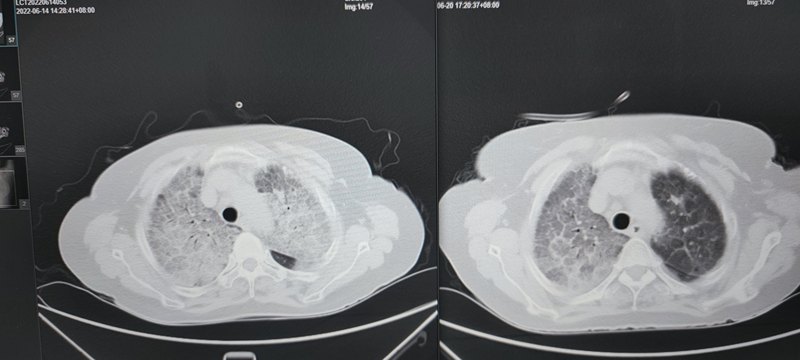

我中心大容量肺泡灌洗前后對(duì)比: